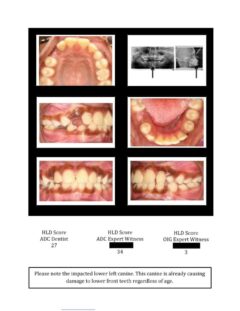

So here again are photos of children’s teeth that were pre-approved for treatment by the state’s Medicaid claims administrator TMHP/ACS, that HHSC-OIG now claims were fraudulently scored by Medicaid dental providers. These cases are from the SOAH hearings that have been completed for Harlingen Family Dentistry and Antoine Dental Center. The SOAH courts found both practices innocent of any allegation of Medicaid fraud or misrepresentation. The photo pages show the attending dentist’s HLD score, the dentist’s expert witness score and the OIG expert’s score.

Antoine Dental Center